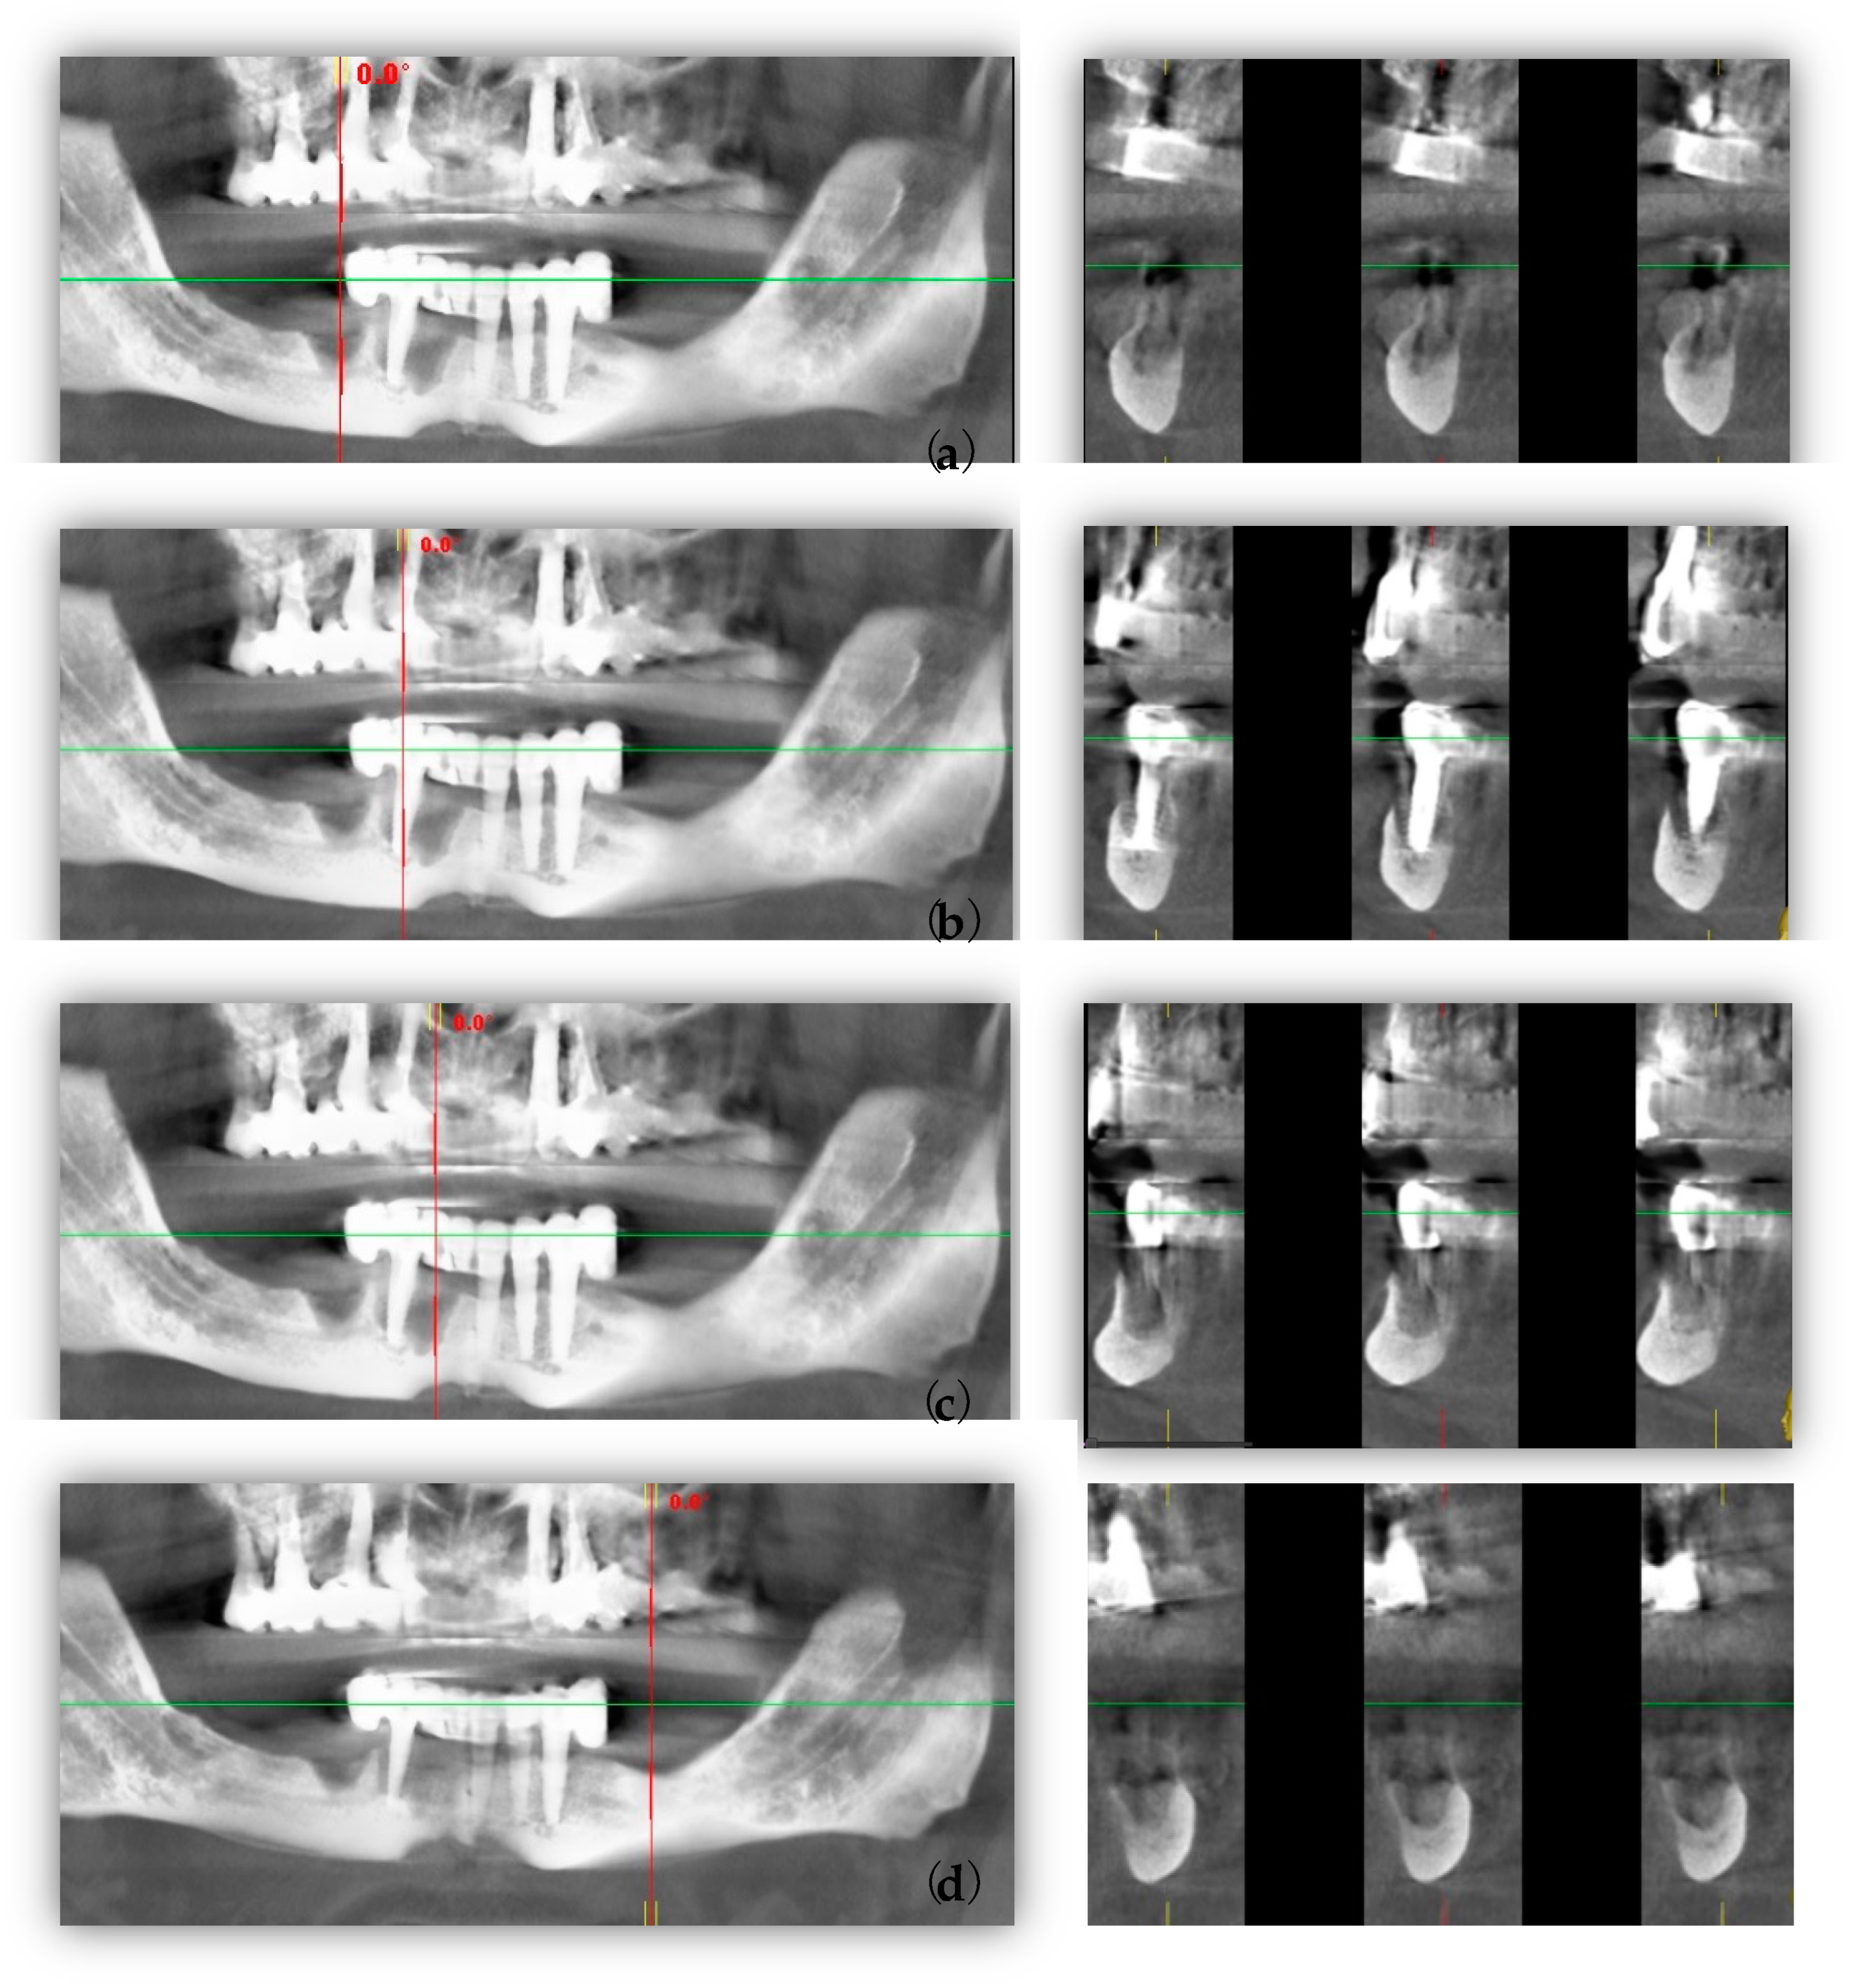

2. Case Report